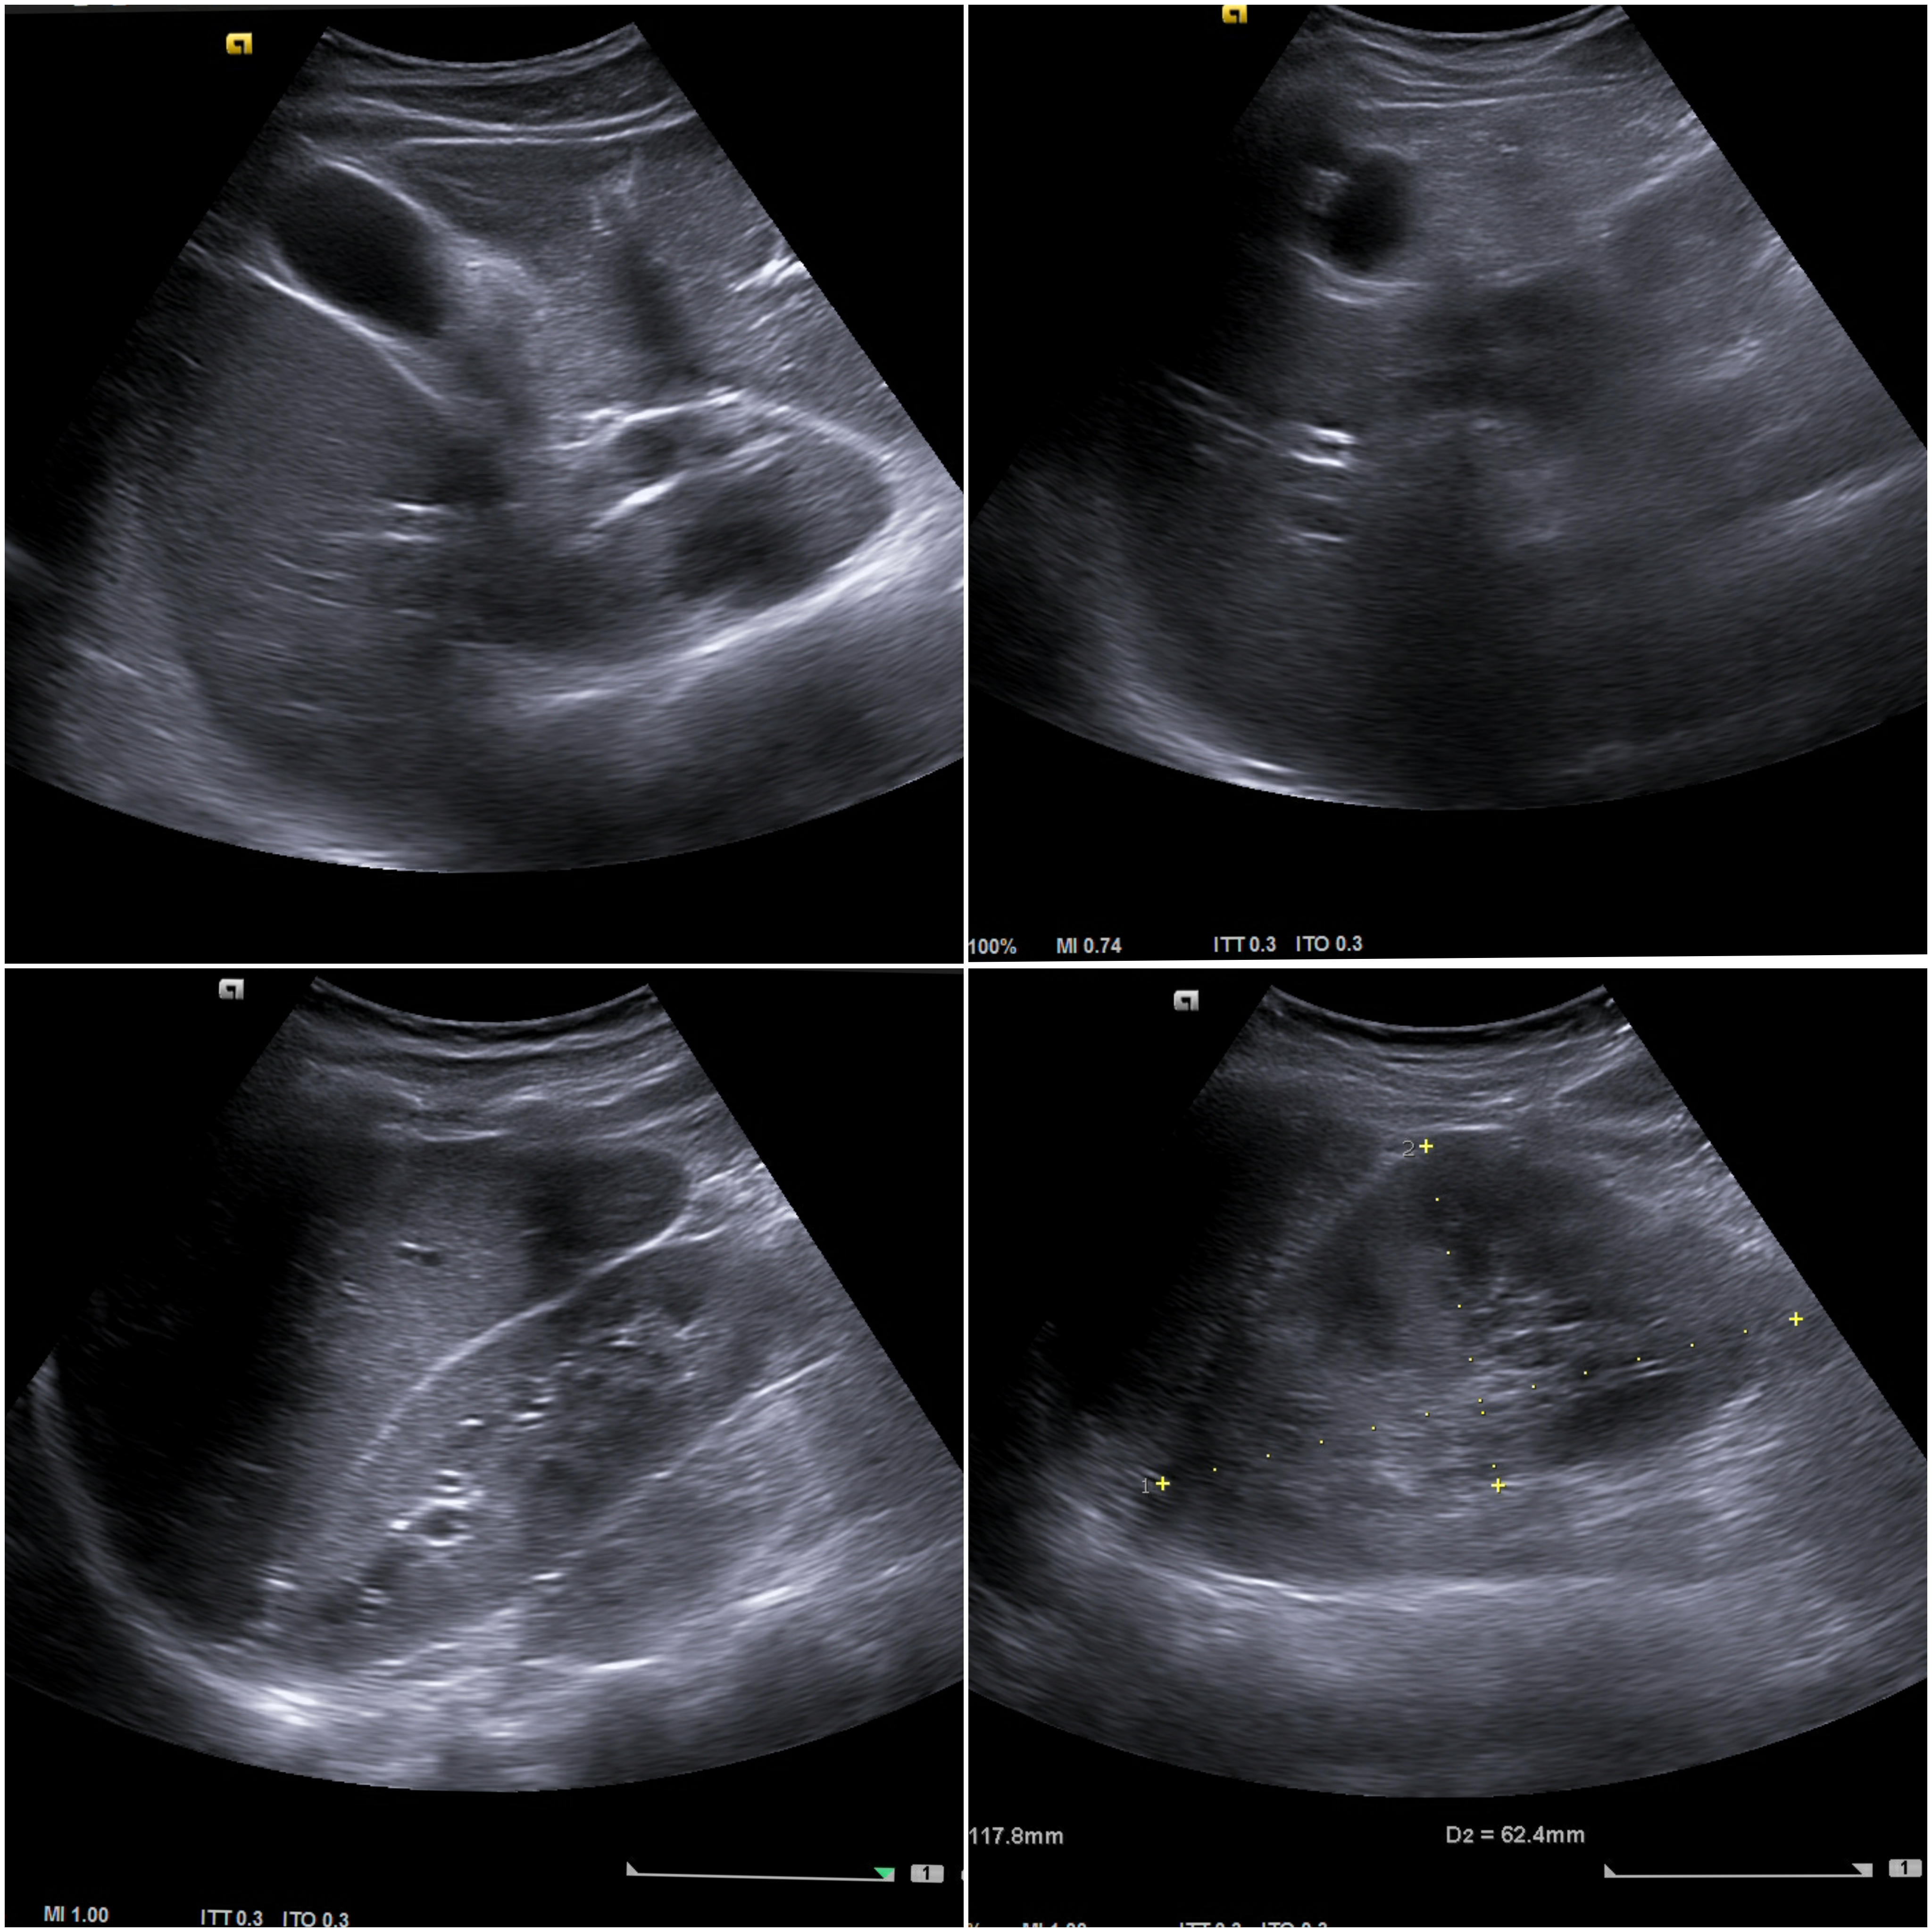

Ecografía clínica abdominal (ventana subóptima):

Parenquima hepatico sin alteraciones, vesícula biliar sin imagenes hiperecoénicas en interior. Pancreas visible en parte, sin alteraciones. Asimetría entre ambos riñones compatible variante de la normalidad RI. Llama la atención dilatación ilíaca derecha al comparar con contralateral y con aorta abdominal distal. Compatible con dilatación aneurismática ilíaca derecha.

La ecografía en Atención Primaria se plantea en el contexto de responder a una pregunta clínica tras la anamnesis y la exploración física u otras pruebas complementarias que se precisen. A resaltar, la importancia de realizar ecografía completa siguiendo una sistemática y prestando atención tanto a variantes de la normalidad como a hallazgos patológicos. En el caso de la ecografía abdominal, es fundamental explorar los grandes vasos tanto en plano transversal como longitudinal, haciendo incapié en la división de las ilíacas.